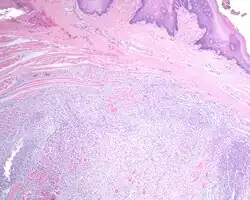

A very low power hematoxylin and eosin stained slide of an ectomesenchymal chondromyxoid tumor. Note the well demarcated tumor, separate from the overlying, intact squamous mucosa.

[1][5][6]

The overlying surface epithelium is intact and unconnected to the well circumscribed, but unencapsulated ectomesenchymal chondromyxoid tumor of the tongue. There are numerous skeletal muscle bundles at the periphery of the tumor.